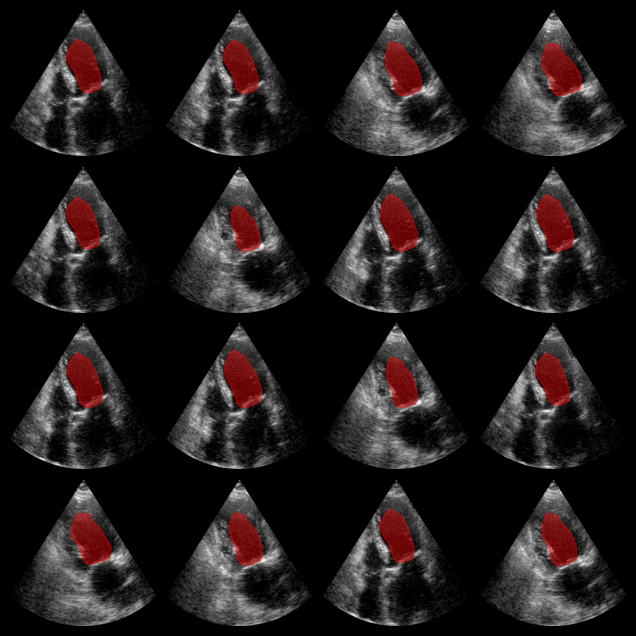

Inference with EchoNetDynamic Model

We first run inference using the EchoNetDynamic model, which expects RGB input images. The model was trained on the EchoNet-Dynamic dataset, but here we apply it to CAMUS data for demonstration.

EchoNetDynamic segmentation results:

The red overlay shows the predicted left ventricle mask for each image.

EchoNet-Dynamic Example Output